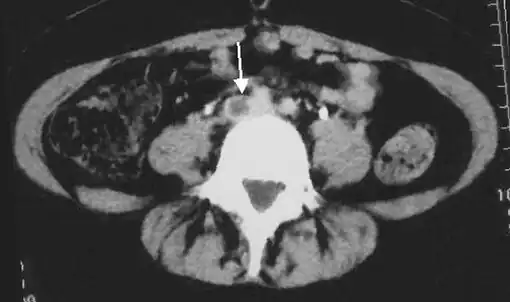

An abdominal CT scan demonstrating an iliofemoral DVT, with the clot in the right common iliac vein of the pelvis

Thrombolysis is the injection of an enzyme into the veins to dissolve blood clots, and while this treatment has been proven effective against the life-threatening emergency clots of stroke and heart attacks, randomized controlled trials[139][140][141] have not established a net benefit in those with acute proximal DVT.[5][142] Drawbacks of catheter-directed thrombolysis (the preferred method of administering the clot-busting enzyme[5]) include a risk of bleeding, complexity,[lower-alpha 12] and the cost of the procedure.[125] Although, while anticoagulation is the preferred treatment for DVT,[125] thrombolysis is a treatment option for those with the severe DVT form of phlegmasia cerula dorens (bottom left image) and in some younger patients with DVT affecting the iliac and common femoral veins.[12] Of note, a variety of contraindications to thrombolysis exist.[125] In 2020, NICE kept their 2012 recommendations that catheter-directed thrombolysis should be considered in those with iliofemoral DVT who have "symptoms lasting less than 14 days, good functional status, a life expectancy of 1 year or more, and a low risk of bleeding."[138]

A mechanical thrombectomy device can remove DVT clots, particularly in acute iliofemoral DVT (DVT of the major veins in the pelvis), but there is limited data on its efficacy. It is usually combined with thrombolysis, and sometimes temporary IVC filters are placed to protect against PE during the procedure.[143] Catheter-directed thrombolysis with thrombectomy[141] against iliofemoral DVT has been associated with a reduction in the severity of post-thrombotic syndrome at an estimated cost-effectiveness ratio of about $138,000[lower-alpha 13] per gained QALY.[144][145] Phlegmasia cerulea dolens might be treated with catheter-directed thrombolysis and/or thrombectomy.[19][143]